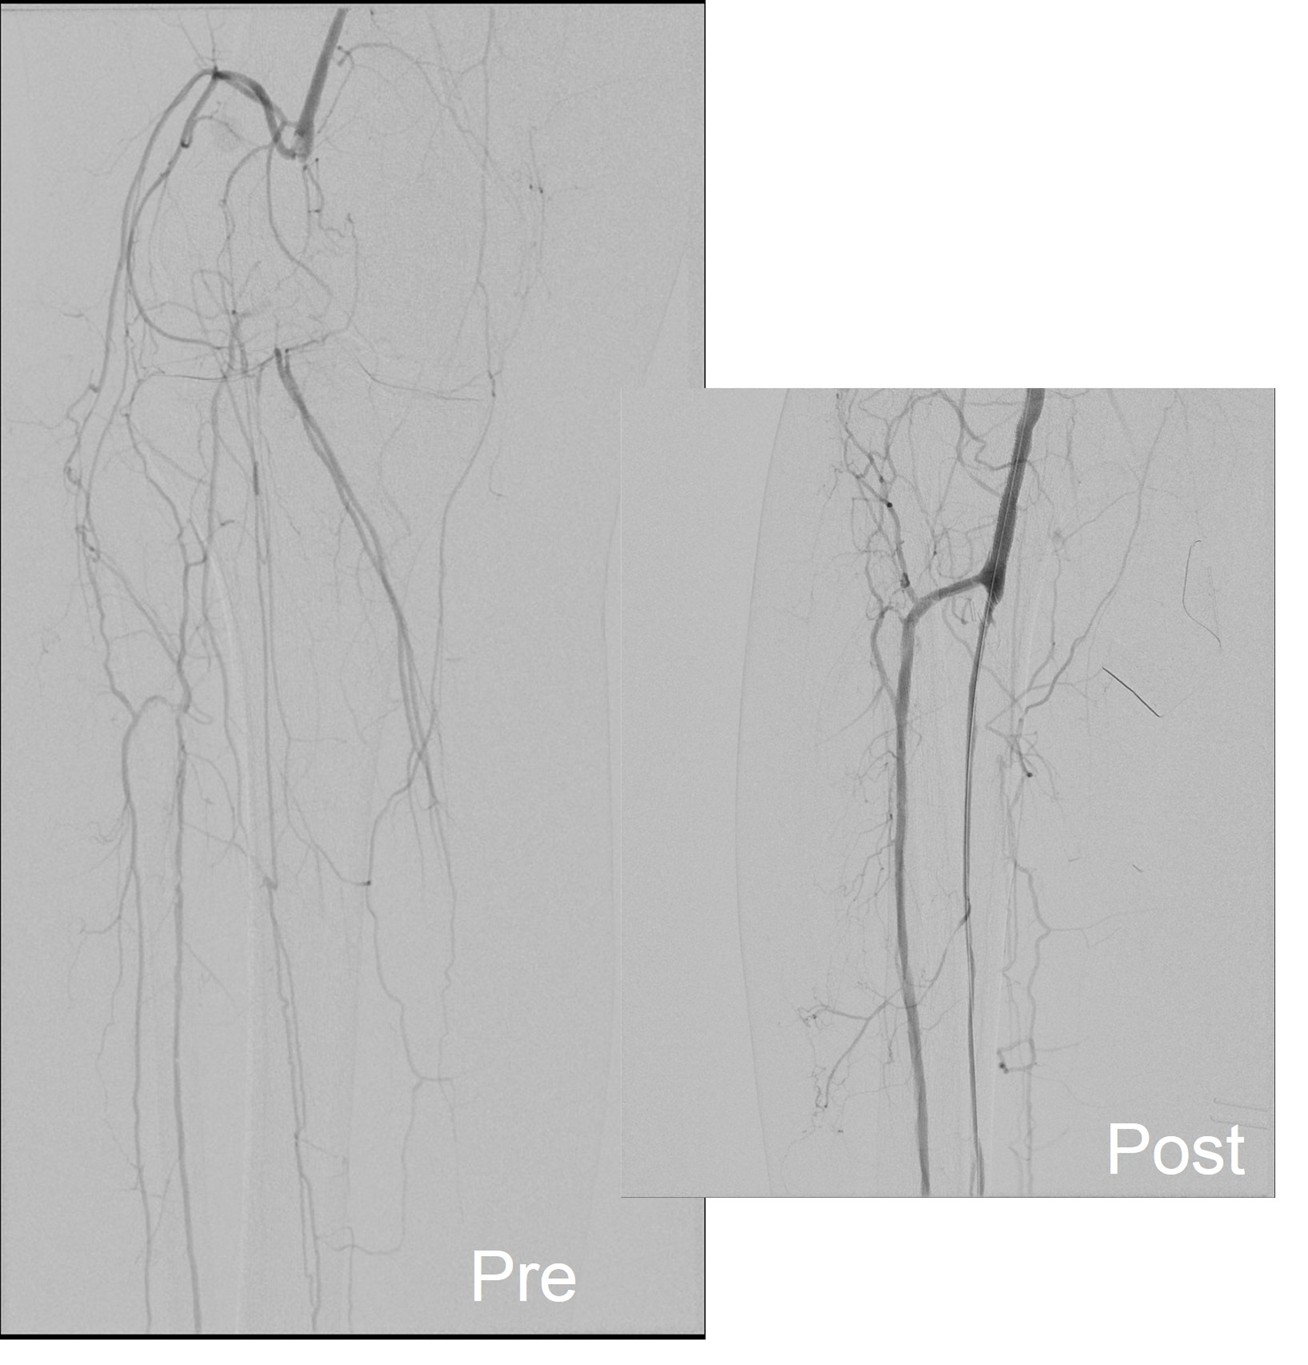

Let me show you one of the first cases I did after returning to Cleveland. I am now practicing at Fairview and Avon Hospitals, premier flagship hospitals in the Cleveland Clinic fleet, on Cleveland’s west side, and a patient arrived while I was on call with sudden onset of pain in his leg from a lack of blood flow. He had occlusive atherosclerotic plaque extending from his external iliac artery to the above knee popliteal artery causing ischemic rest pain.

I contacted LeMaitre Vascular and got in touch with your representative, L. Fisher, who promptly sent the Moll Ring Cutters I needed to perform a remote endarterectomy of the patient’s occlusive external iliac and superficial femoral artery plaque. The technical details of remote endarterectomy are have been covered in my blog (https://vascsurg.me/?s=endore), but in the end, through a 7cm incision in the groin (don’t believe the hype, this is minimally invasive), I restored his arteries to their original open condition. Shown below are the results. It was with great sadness that I heard that the LeMaitre Vascular equipment being sent were the last of the stock available in North America. The patient did very well, with the operation completed well before lunch, and is recovering rapidly from his small wound and big rescue. He gets to walk out of the hospital on two legs, but also with the surety that he avoided a major bypass operation, and avoided the short term gains of stenting from the aorta to the profunda -more peel packs and landfill items and a dubious long term durability. Hey, I even used a XenoSure patch on the common femoral.